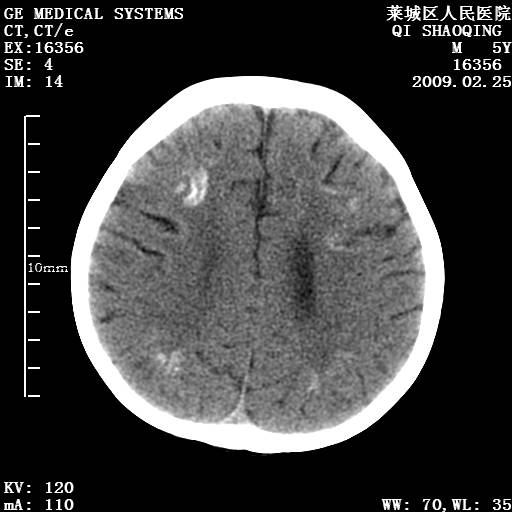

以下是引用wangzhengyuan在2009-2-28 10:22:00的发言:[br]甲状旁腺功能减退引起的脑改变.

以下是引用zsl6918在2009-2-28 10:17:00的发言:[br]首先考虑甲状旁腺功能低下所致,可结合实验室检查明确.另外需除外先天性宫内感染所致.

以下是引用余辉在2009-3-1 9:35:00的发言:[br]患者明显的肢体及智力改变,不支持fahr病,多考虑甲旁低,有可能伴有甲低(呆小症).进一步检查。